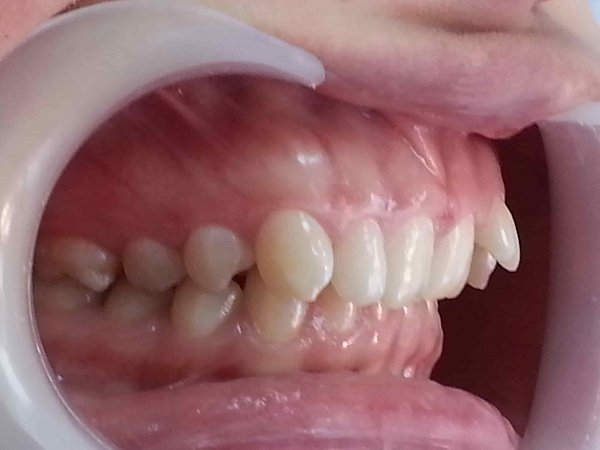

Дистальная окклюзия, глубокая травмирующая резцовая окклюзия. Лечение на брекет-системе две челюсти, техника MAEW с удалением нижнего зуба мудрости слева. Срок лечения 2 года 2 месяца.